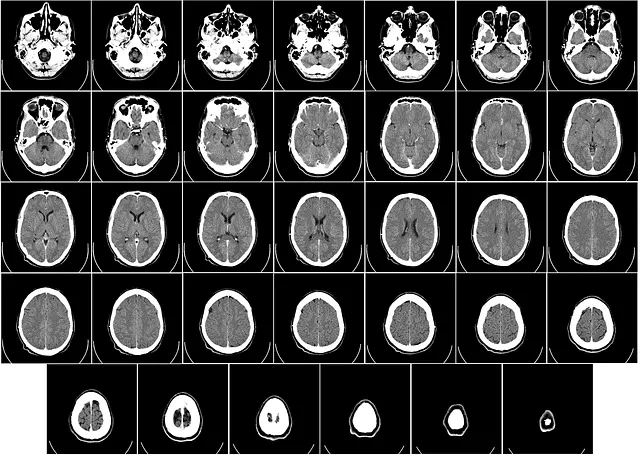

CT촬영은 Computer Tomography의 약자로 우리말로하면 전산화 단층 촬영이라고 합니다. 즉 방사선을 신체에 투과하여 혈관이나 뼈 등 인체조직을 살펴보는 방사선 검사 방법입니다. 조금 더 구체적으로 말하면 정상 조직과 병변 조직을 구분하는 목적이 있습니다. 엑스레이는 단면을 찍지만 CT촬영은 연속적으로 사진을 촬영하기 때문에, 더 세밀하며 입체적인 분석이 가능합니다. 때문에 골절, 혈관 그리고 종양 검사 등 아주 광범위하게 쓰이고 있습니다.

| 두부 | 뇌출혈, 뇌경색, 뇌종양 등 |